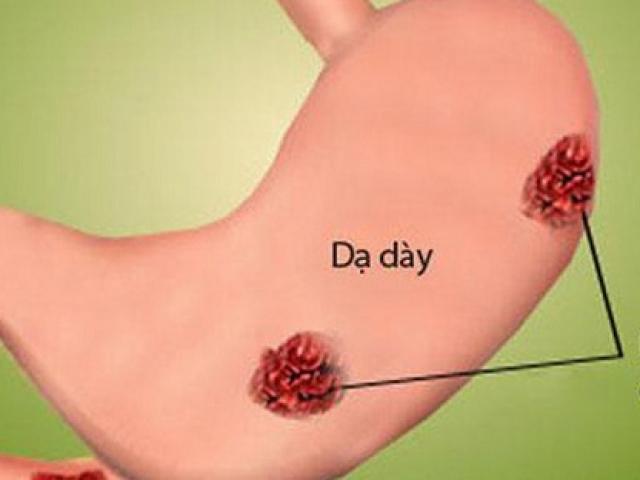

2. Đau bụng

Đau bụng, buồn nôn, nôn là một số triệu chứng phổ biến trước cơn đau tim. Dấu hiệu này chung ở cả nam và nữ.

Mô tả: Nếu là đau bụng cảnh báo đau tim thường sẽ đến theo từng cơn. Thường xuyên làm việc nặng cũng có thể là nguyên nhân khiến những cơn đau trầm trọng hơn.

Mô tả: Đau ngực có thể mở rộng cảm giác không thoải mái ở cả 2 bên cánh tay (thường là bên trái), hàm dưới, cổ, vai hoặc dạ dày.